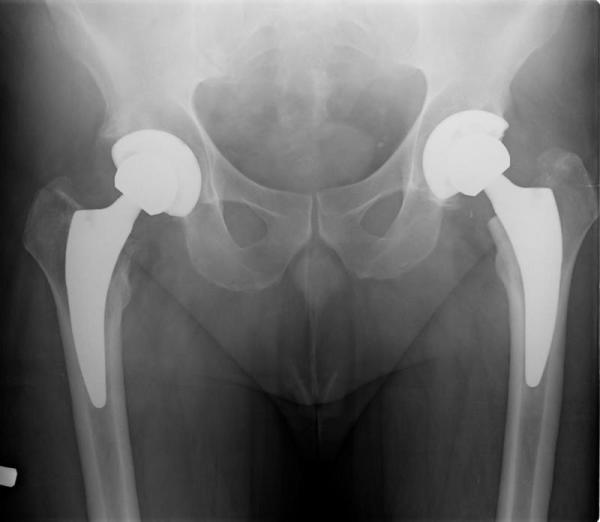

ENDOPROTEZOPLASTYKA STAWU BIODROWEGO

Jest to metoda leczenia zaawasnowanych zmian zwyrodnieniowych stawu biodrowego, której celem jest eliminacja dolegliwości bólowych oraz poprawa zakresu ruchu chorego stawu. Zabieg wykonuję z dostępu przedniego małoinwazyjnego MIS DAA. Pozwala on na dotarcie do stawu w przedziałach międzymięśniowych bez uszkodzenia mięśni. Zaletą tego dostępu jest mniejsza utrata krwi, mniejsze ryzyko zwichnięć pooperacyjncyh stawu, szybsze usprawnianie chorego oraz krótka kosmetyczna blizna. W zależności od wieku chorego stosuję implanty "klasyczne" lub "krótkie" trzpienie przynasadowe. Zabieg wykonywany jest najczęściej w znieczuleniu podpajęczynówkowym. W pierwszej dobie pooperacyjnej pacjent jest pionizowany i rozpoczyna rehabilitację. Średni czas hospitalizacji wynosi 4-5 dni. Przeprowadzam ponad 120 tego typu operacji rocznie.